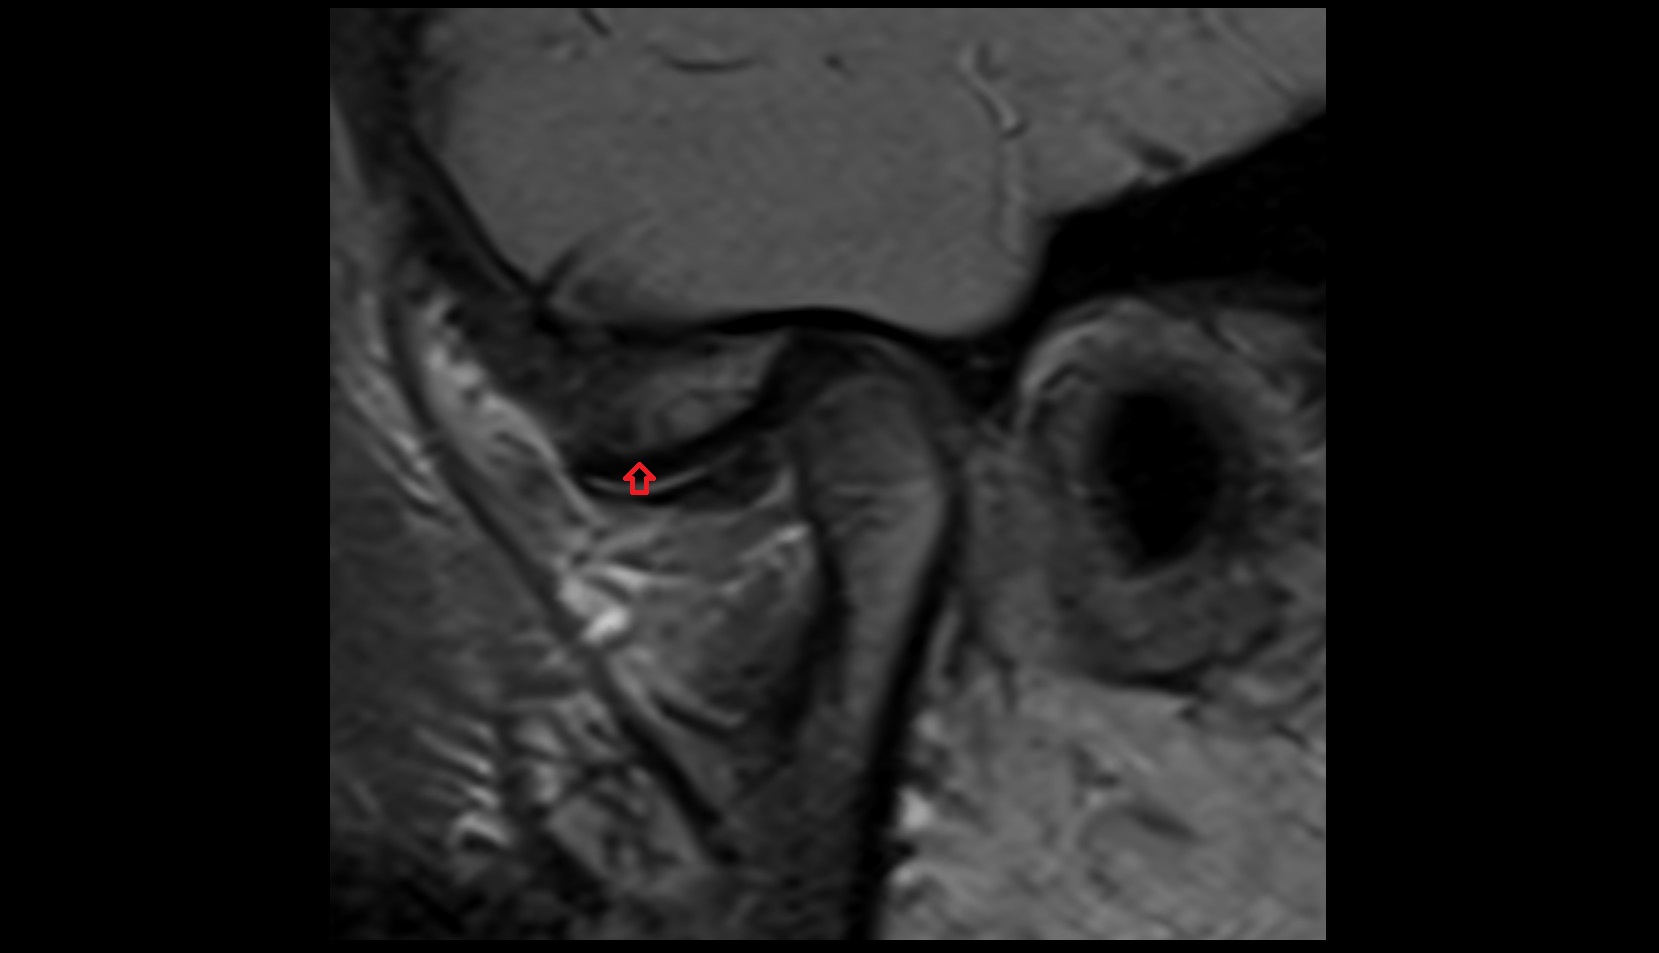

- Temporomandibular joint

- Articular disc of temporomandibular joint

- Articular eminence

- Mandibular condyle

- Mandibular fossa